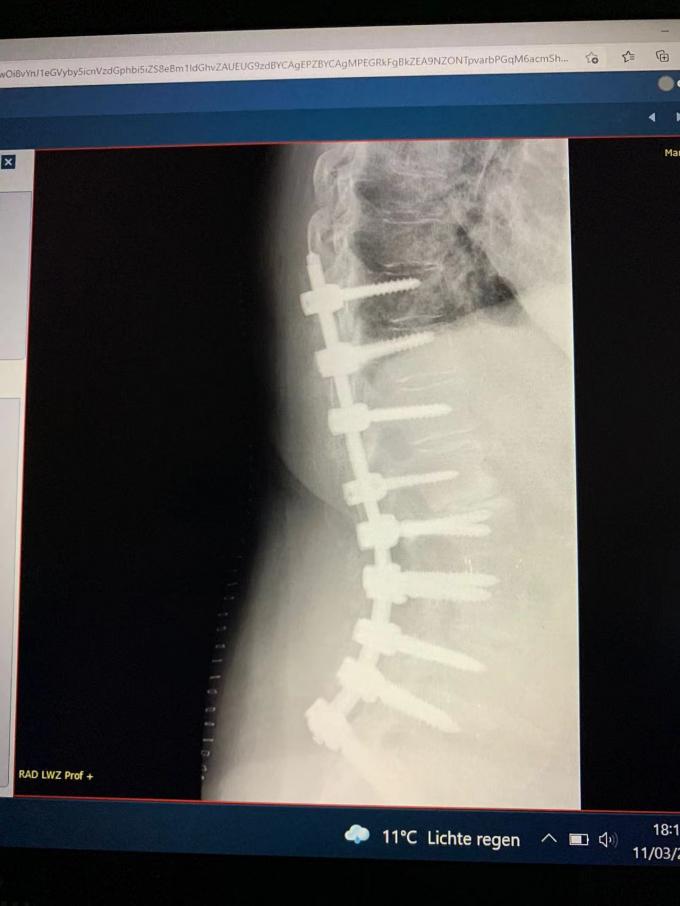

Dieses Mal, haben wir einen anderen Fall spinaler Schraubenchirurgie geholt. Das Bild zeigt den Röntgenstrahl nach der erfolgreichen Operation. Es kann dass, nach der Anwendung unseres spinalen Schraubenstangensystems gesehen werden, der Dorn des Patienten tadellos geregelt worden ist. Ein großes danken Ihnen zu unserem orthopädischen Doktor, der perfekt war.